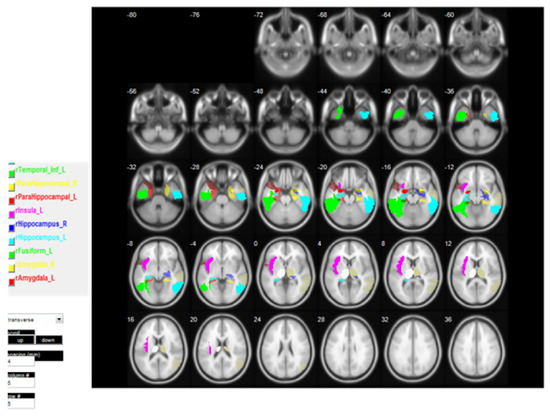

These ROIs are identified based on the t-map generated from VBM analysis. The regions which are significantly different and bundled into the same region are considered as a cluster, as shown in Figure 4, Figure 5 and Figure 6. The generated clusters vary in shape and size, based on the significance of the p-values and the error correction used; p-value was computed based on a repetitive experiment in the range 0.1 to 0.0001, the one with the highest voxel number is reported i.e., p< 0.001. Thus, we have selected for p < 0.001 where 14 clusters were selected out of 30 clusters from the t-map of GM volumes, and one cluster from the t-map of the WM volumes both from the AD and CN two-sample t-tests. Similarly, three clusters were generated from the t-map of the GM volumes of the CN and MCI two-sample t-tests. The selected 18 clusters were used as ROI directly to obtain the mean weighted voxel value from each participating MRI; we will term this ROI as ROI_CL hereinafter. The number of voxels in each ROI_CL differs abruptly so, if we accumulate all the voxels from each ROI, the number of voxels is going to be substantially large; hence one of the logical solutions would be taking mean weighted voxel value as stated in Equation (2) to represent a single value for each selected ROI for each MRI, demonstrated as shown in Appendix A, Table A1.

Each participant’s brain differs in terms of the structure and size of the anatomic regions. This can be more problematic when anatomical ROIs are defined from a single participant and applied to the remaining data, as a significant anatomical inconsistency exists between the participants. Hence, we selected anatomic regions with a higher number of voxels in each cluster. After obtaining those regions, we generated a mask from the automated anatomic labeling (AAL) [34] atlas for those anatomic regions and co-registered with our t-map image. The AAL atlas is a digital human brain atlas with 116 labelled volumes indicating macroscopic brain structures. Hence, these masks can be used subsequently for feature extraction. The most significant regions of the brain based on the t-map image using AAL atlas labels are tabulated in Table 2 and Table 3 for the ADNI and the GARD test conditions, respectively. From the tables, 14 anatomic regions were selected, and the standard ROIs were generated from the AAL atlas, as shown in Figure 7. We will term this ROI as ROI_AAL hereinafter. We applied the same weight-based mean calculation to obtain the mean features to represent each ROI value from all MRI, as in ROI_CL, a few demonstrated as in shown in the Appendix A, Table A2.

For VBM-based ROI, the selection was done manually based on cluster size, ROI_CL, for which we selected the cluster with the highest number of voxels, e.g., AD vs. CN voxels result from the ADNI dataset t-test yielded 30 clusters, of which we selected 14 clusters with significant voxel numbers, while rest small-sized clusters were neglected (please refer to the Supplementary Data file ADNI_AD_CN_p0.001_FWE_BrainLabels). Similarly, the remaining four clusters were selected from the AD vs. CN WM t-test and CN vs. MCI t-test (please refer to the Supplementary Data file ADNI_CN_MCI_p0.001_FWE_BrainLabels). For ROI_AAL the selected clusters were matched with the AAL template, to obtain significant anatomic regions, then those standard ROIs were used to create the mask for further voxel detection from each ROI, for feature detection. On initial matching 23 ROI from AD vs. CN (16 GM and seven WM), nine ROIs from AD vs. MCI, and 11 ROIs from CN vs. MCI were detected. We selected the one with the highest number of voxels from each cluster and the overlapped regions. In total there were 18 ROIs from the cluster and 14 ROIs from the AAL atlas, as shown in Figure 6 and Figure 7, which were tested separately to obtain the best classification result.

Table 4 presents the clinical ROIs found on t-test group comparison between participating class domains; it lists the important brain regions identified using AAL matching. There were majorly six clusters to distinguish the voxel intensities, with Left Temporal Inferior Lobe, both Right and left Thalamus, left and right Amygdala, left Fusiform, left Insula, and right Hippocampus being the prominent ones for CN versus AD, at p < 0.001, whereas left and right Hippocampus, Temporal mid lobe, right Parahippocampal region were highlighted as dense cluster for CN versus MCI. Details of all the clusters and numbers of voxel detected are presented in Supplementary files. The ROIs identified using ADNI datasets are clearer and larger whereas GARD datasets are smaller and dimmer, (please see Figure 4 and Figure 5) which may be due to the difference of MRI acquisition protocol [41], still the regions like the hippocampus, Amygdala, Temporal lobe, Thalamus are commonly deteriorated during AD/ADD and MCI/mAD (please see Table 2 and Table 3, the T-value measures the size of the difference relative to the variation in the group data. A higher T-value supports our null hypothesis of group difference condition. SD of T represents the standard deviation measure of T-value and mean-T, the mean value of all T-values for voxels in its cluster). As it is believed that the loss of memory is mostly related to the limbic system including its subcortical structures like Hippocampus, Amygdala, more prominent in the left hemisphere [42]. However various cortical structures including frontal, Parietal, Temporal lobes are also affected during neurodegeneration [43,44]. Hence, it is wise to state that overall brain structures associated with memory are affected during the AD memory dysfunction phase.

Figure 6. ROI_CL selected from the cluster of AD < CN (p < 0.001).

Applsci 11 06175 g006

Figure 7. ROI_AAL selected from the cluster of AD < CN (p < 0.001).

Applsci 11 06175 g007